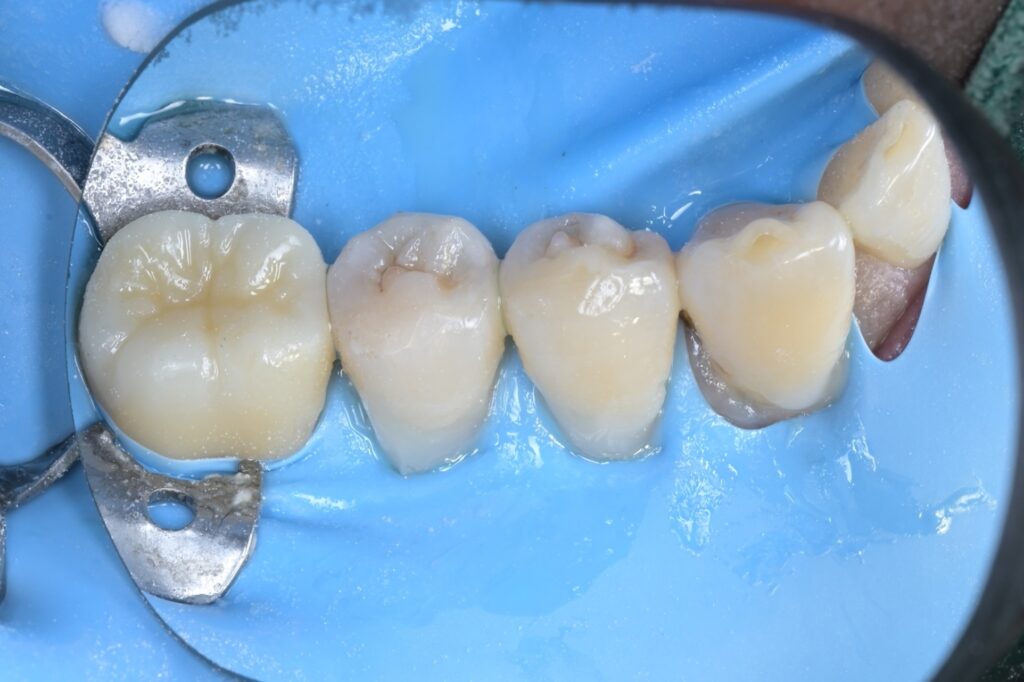

STEP 1. 문제 치아 확인 (제2소구치)

가장 먼저 뒤쪽에 있는 작은 어금니(5번 치아)부터 치료를 시작합니다. 러버댐을 걸어 치아만 격리했지만, 잇몸 아래쪽 깊숙이 충치가 숨어 있는 것이 보입니다.